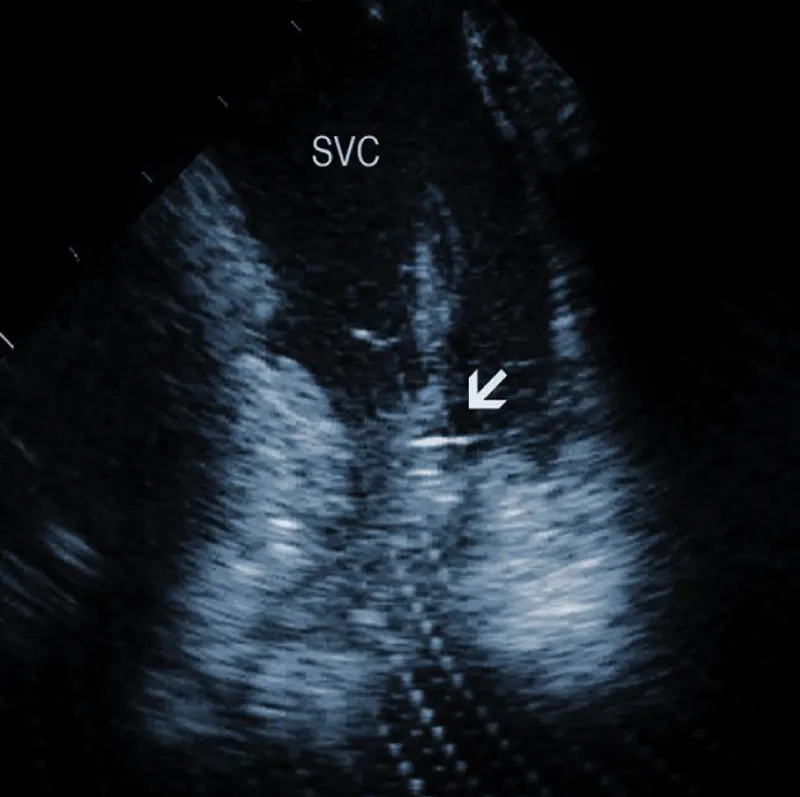

Residuals after TLE: Residual fibrotic tissue after TLE, called ghosts, has been described as a new phenomenon in cardiology (Figure 4). The presence of ghosts was first described by Rizzello, et al. using ICE [22]. Caiati, et al. studied a cohort of 40 patients using ICE before and after TLE to document the relationship between thrombotic or fibrotic reactions to the lead and with subsequent occurrence of ghosts [23]. ICE could identify thickened lead (thickness ≥ 1 mm than the vendor declared thickness in at least one lead) and fibrotic attachment to the cardiac wall in a substantial number of subjects. Thickening was noted in 25/40 patients (62%) overall, involving the atrial (2 patients (5%)) or the ventricular (9 patients (22.5%)) or both leads (14 patients (35%)). The fibrotic attachment was observed in 12/40 patients (30%). Both thickening and fibrotic attachments were significantly associated with subsequent ghosts (p < 0.001 and p = 0.002, respectively), but lead thickening had a higher prediction power. Narducci, et al. demonstrated that the presence of ghosts could be associated with a worse prognosis in device-related infective endocarditis [24]. Analyzing 217 TLE cases, the authors identified ghosts in 30 (14%) patients after TLE. In their study, endocarditis was one of the independent predictors of the presence of ghosts. Poterala, et al. detected ghosts after TLE in 19% of cases [25]. These residual fibrotic tissues were most often located along the originally implanted lead’s route. The local infection and infective endocarditis were associated with a larger number of ghosts after the removal procedure (p = 0.006). Besides frequent association with infection, detection of ghosts after TLE is also important for other reasons. Otherwise, they can be mistakenly interpreted in the echocardiographic examination as new pathological structures of unknown origin. In such a situation, the patient can be subject to unnecessary anticoagulant therapy, invasive diagnostic procedures, and/or cardiac surgery. Given the potential risks of ghosts, their presence should probably be noted on post-extraction imaging and might warrant closer post-extraction follow-up [4].

Figure 4: Ghosts within the superior vena cava (SVC) after removal of the ICD leads marked by arrows. AO: Aorta.